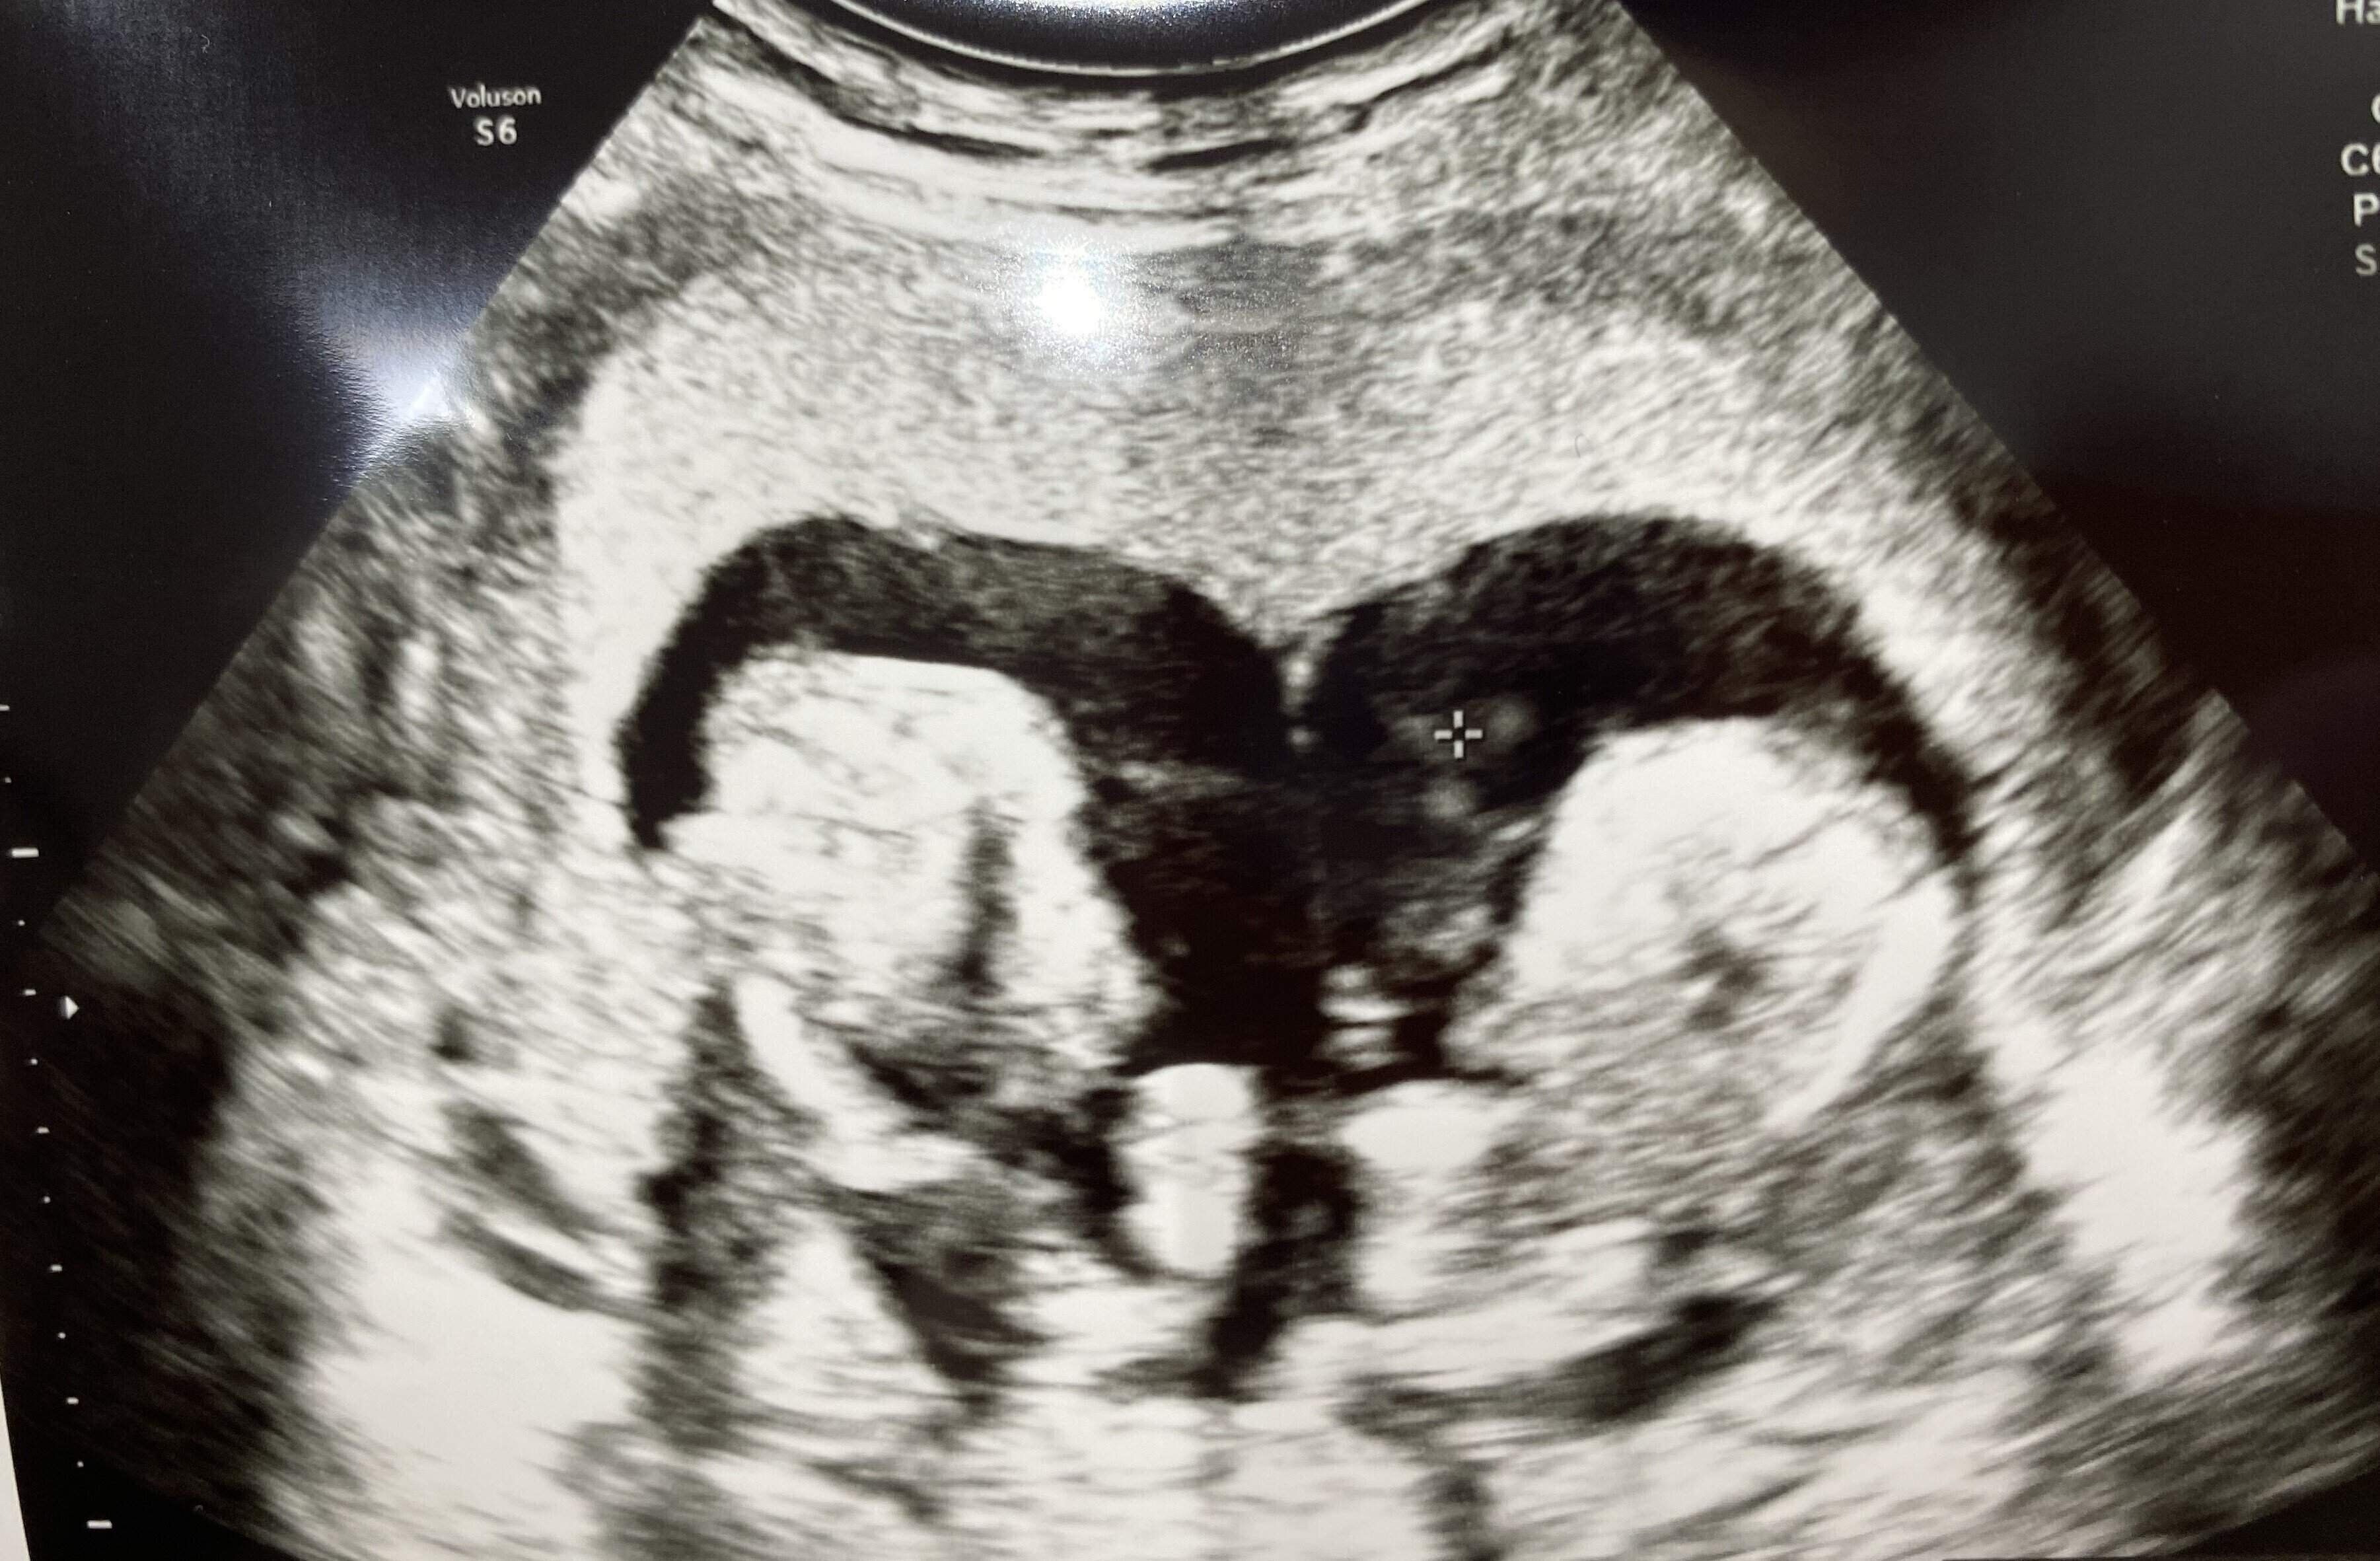

「医師に『あれっ?2人いるよ』と言われて。まったく予期していないことで、すごく驚きました。もちろん、2人を妊娠した喜びやうれしさはあったんですが・・・、私たち夫婦は共働きで、互いの実家も気軽に頼れる距離にはないので、仕事と育児をどうやって両立したらいいのかも不安でしたし、2人子どもが増えるとなるとお金もそれだけかかるわけですから、育てられるのかという不安もありました。

診察の結果はやはり破水でした。まさか妊娠14週で破水することがあるなんて。双子は二卵性でそれぞれが卵膜に包まれていたのですが、二男の卵膜の内側にあるはずの羊水がほとんどなくなっている状況でした」(河原さん)

毎日、医師や看護師さんがおなかの赤ちゃんの心音を確認してくれました。その音を聞いて『今日も生きている』と少しだけほっとする日々。エコー検査の日には、動いている姿を見ることもできました。幸運にも大きな変化はなく、2人の心臓は動き続けてくれました」(河原さん)

「妊娠22週を過ぎた日の診察で、医師から『正直、よくも悪くもならずこの状況が続くと思いませんでした』と言われたんです。その言葉に、うれしくて笑ってしまいました。2人の生命力はすごいな! って。